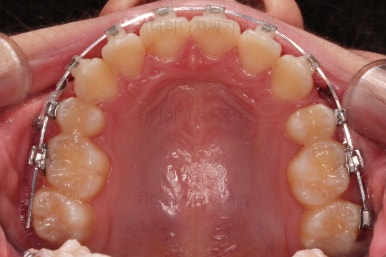

초진 시 입안의 모습입니다.

위아랫니가 많이 삐뚤진 않는데 뭔가 이상하죠?

어금니 맞물림은 지그재그로 잘 맞물려 있는데 위아래 앞니는 서로 앞뒤로 매우 멀죠.

비밀은 매우 자연스러워 보이지만 아래 앞니 2개가 선천 결손인 상태였습니다.

앞니끼리 맞물리지 않다보니 아래 앞니는 점점 솟구쳐 과개교합(깊게 맞물려 아래 앞니가 거의 보이지 않는 현상)이 되게 됩니다.